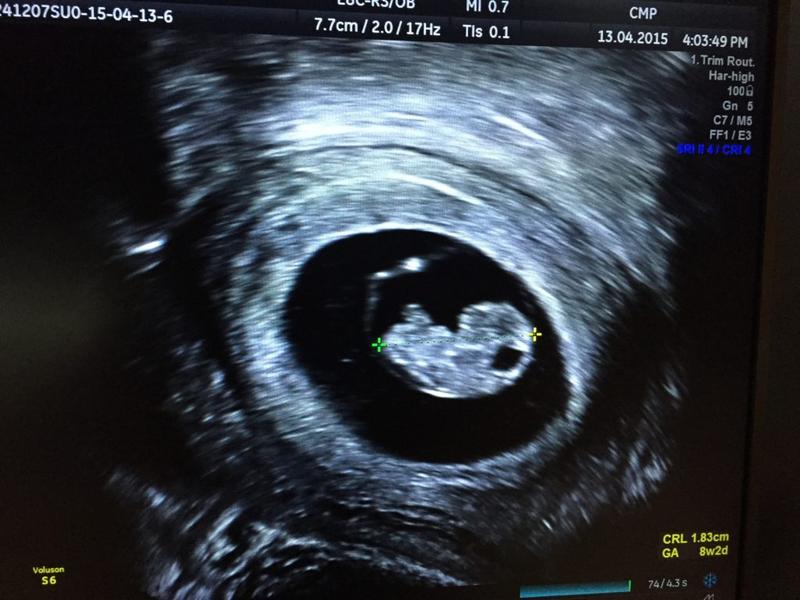

Rozwój zarodka w trzecim tygodniu ciąży to prawdziwy rollercoaster! W tym okresie mały człowieczek w twoim brzuchu rozpoczyna swoje pierwsze kroki, a tak naprawdę pierwsze podziały komórkowe. To właśnie teraz zarodek zdobywa miano blastocysty, jednak ostrzegam, że nie przypomina jeszcze malutkiego człowieka, raczej wygląda jak mini ryba z kijankowatym rodowodem. W końcu stawiamy na nowoczesność, a nie na przestarzałe schematy, prawda?

W tym tygodniu zachodzą ogromne procesy, które budują fundamenty dla przyszłego maleństwa. Zarodek dzieli się na trzy magiczne warstwy: ektodermę, mezodermę oraz endodermę. Z ektodermy rozwinie się wszystko związane z układem nerwowym, mezoderma zadba o serduszko oraz mięśnie, natomiast endodermę układ pokarmowy. Kierunki kariery młodziaka są więc obiecujące, musisz jednak pamiętać, że nadal jest on mikroskopijny, nawet bardziej niż twoje najciemniejsze sekrety!